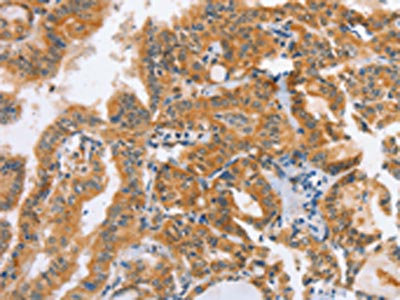

The image on the left is immunohistochemistry of paraffin-embedded Human liver cancer tissue using CSB-PA695560(DDX58 Antibody) at dilution 1/70, on the right is treated with synthetic peptide. (Original magnification: ×200)

The image on the left is immunohistochemistry of paraffin-embedded Human thyroid cancer tissue using CSB-PA695560(DDX58 Antibody) at dilution 1/70, on the right is treated with synthetic peptide. (Original magnification: ×200)